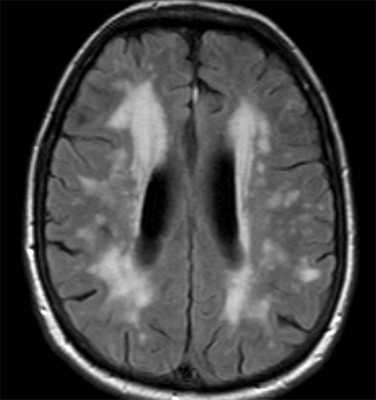

При МРТ ствола мозга регистрируются симметричные, иногда билатеральные очаги. Наиболее часто поражаются черная субстанция, в особенности ее ретикулярная часть, покрышка моста и среднего мозга, нижние бугры четверохолмия. Билатеральная гипертрофическая дегенерация ядер олив была описана в 40% случаев у пациентов с заболеваниями обмена веществ, что заставляет предположить, что нижние ядра олив поражаются при синдроме Лея как из-за первичной метаболической уязвимости, так и от вторичной транссинаптической нейрональной дегенерации. При синдроме Лея поражение ствола может также сопровождаться билатеральными и симметричными очагами в базальных ядрах и диффузной супратенториальной лейкоэнцефалопатией. При синдроме Лея описывается также поражение мозжечка с формированием отека с петехиальным компонентом, что позволяет предполагать наличие микроангиопатии. Гибель клеток Пуркинье и мозжечковая атрофия при синдроме Лея возникает, как предполагается, вследствие эксайтотоксичности.

Описано мультисистемное митохондриальное заболевание, специфически поражающее проводящие пути белого вещества, которое называется лейкоэнцефалопатией с поражением ствола головного мозга, спинного мозга и повышенным накоплением лактата (LBSL). Данное состояние ассоциировано с различными генетическими отклонениями, в частности с мутациями гена DARS2. При этом синдроме описано билатеральное симметричное поражение белого вещества медиальной петли, тригеминальной петли, пирамидных трактов, задних канатиков спинного мозга, верхних и нижних ножек мозжечка, белого вещества мозжечка; при МР-спектроскопии выявляется увеличение уровня лактата.

Гипертрофическая дегенерация ядер оливы считается специфической формой транссинаптической гипертрофической дегенерации и развивается вследствие неспецифического повреждения денто-рубро-оливарного пути. Хотя это состояние у детей считается редким, сообщается о его превалировании у пациентов с метаболическими заболеваниями, а также после операции по поводу опухолей задней черепной ямки. На МРТ выявляются Т2-гиперинтенсивные очаги, часто с билатеральным и симметричным увеличением оливарных ядер. Они начинают появляться в течение месяца после острого события и в течение 3-4 лет имеют тенденцию к разрешению.